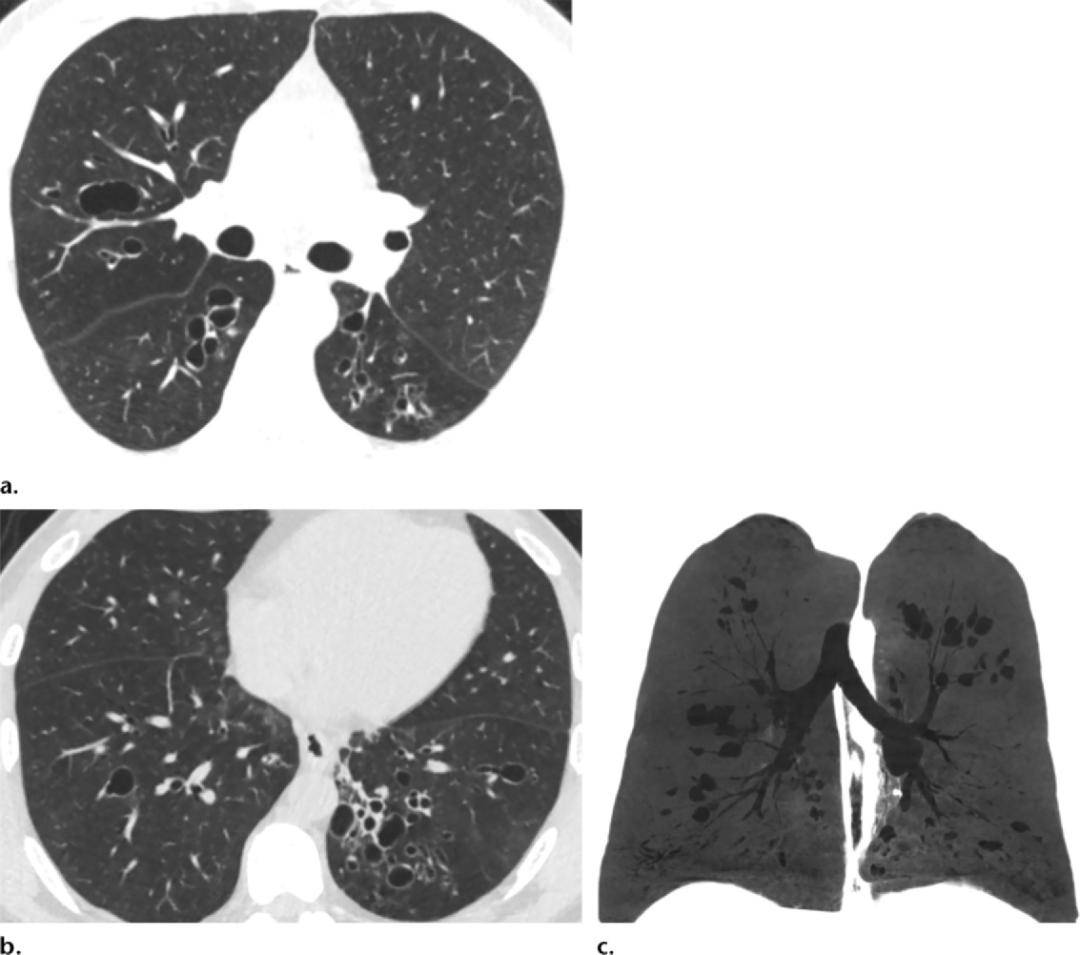

胸部x线检查可见以基底前部为主的小结节,支气管扩张,肺不张或瘢痕(图